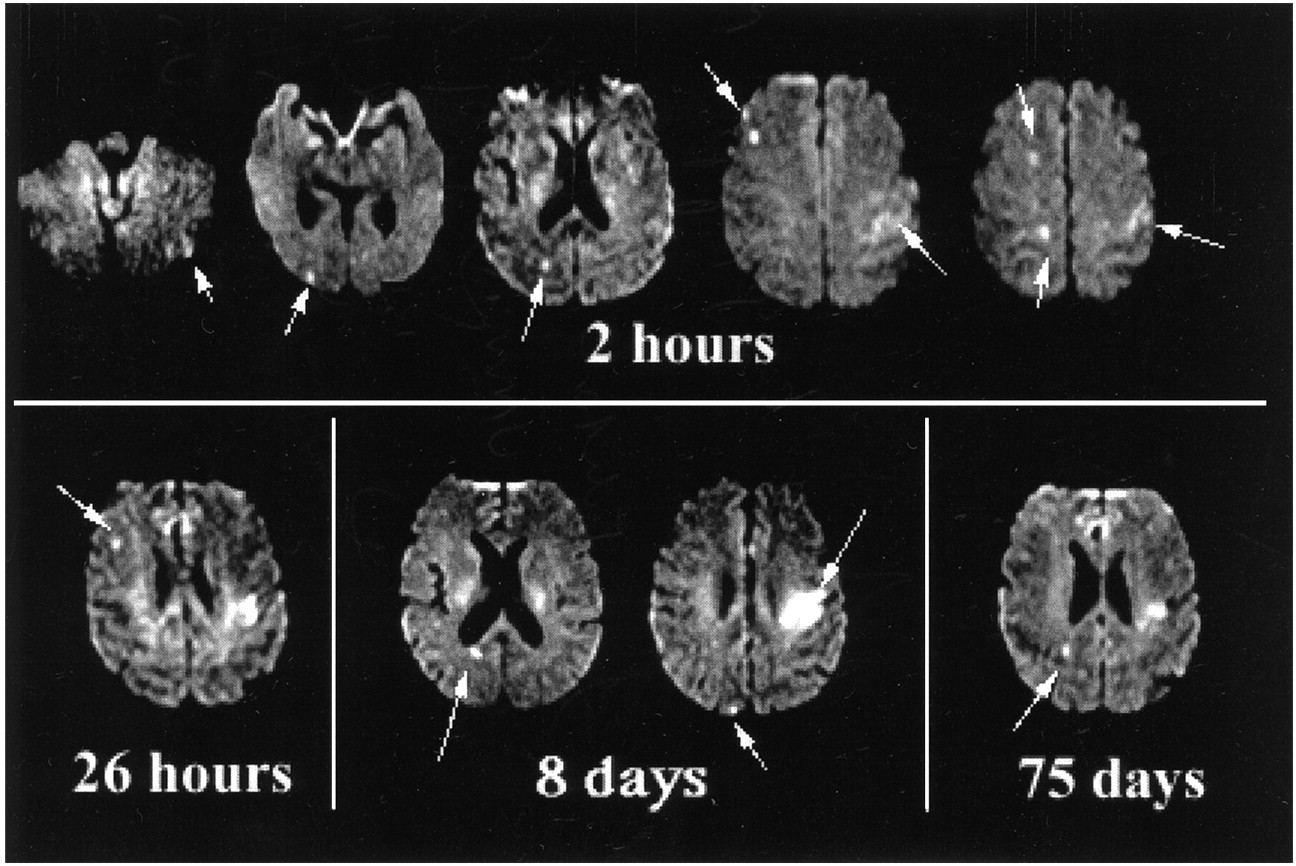

多个沉默脑缺血性病变在时间和空间上发生在一个58岁的男人与一个未经处理的左心室心脏血栓。1 - 2这个病人最初面对突然出现的表达语言障碍,右侧虚弱和低血压,有心肌梗死病史的,可怜的左心室功能。第一先生diffusion-weighted成像(驾车)研究了两个小时后出现症状。hyperintense地区(箭头)表明急性缺血性损伤。醉酒驾车病变出现在左额叶区域,右侧大脑半球,左侧小脑半球。串行先生研究新发现了小病变临床沉默。26小时,8天新病变发展在右大脑半球(箭头)。左侧额叶病灶显示病变与hyperintensity进化的迹象,一些肿大。在75天的一个新的病变出现相邻侧脑室后角的权利。多角度顶端血栓随后被发现。先前的流血事件杜绝抗凝,直到这个时间。

1。Baird AE, Lovblad KO, Schlaug G, Edelman RR, Warach美国多个急性中风综合症。栓塞性疾病的标志吗?首页神经学2000;54:674 - 678。

2。Caplan LR Babikian六世。大脑栓塞变量特色是一个动态的过程。首页神经学2000;54:797 - 801。